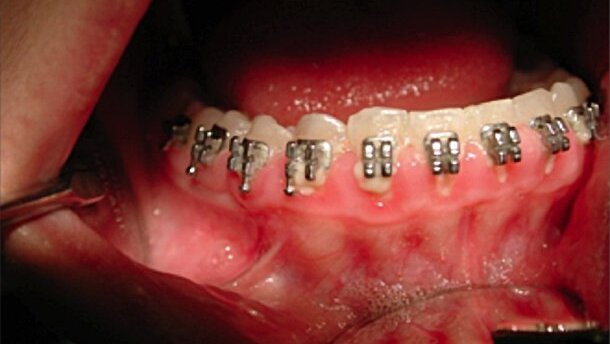

Nel caso qui presentato, gengivite ipertrofica da apparecchio ortodontico, si evidenza come l’utilizzo del Laser CO2 coadiuvato da LED sia, al contempo, poco invasivo e garantisca una totale guarigione dei tessuti notevolmente accelerata.

In questo caso di gengivite ipertrofica è evidente una forte presenza di placca, sia in arcata superiore, sia in arcata inferiore (Figg. 1-4).

Per l’intervento di gengivoplastica viene qui utilizzato il Laser CO2 Ultrapulsato MX7000 e il biostimolante LED-Phaselight, le cui proprietà antiedemigene e antiinfiammatorie, sono da tempo scientificamente riconosciute e validate (Figg. 5, 6).